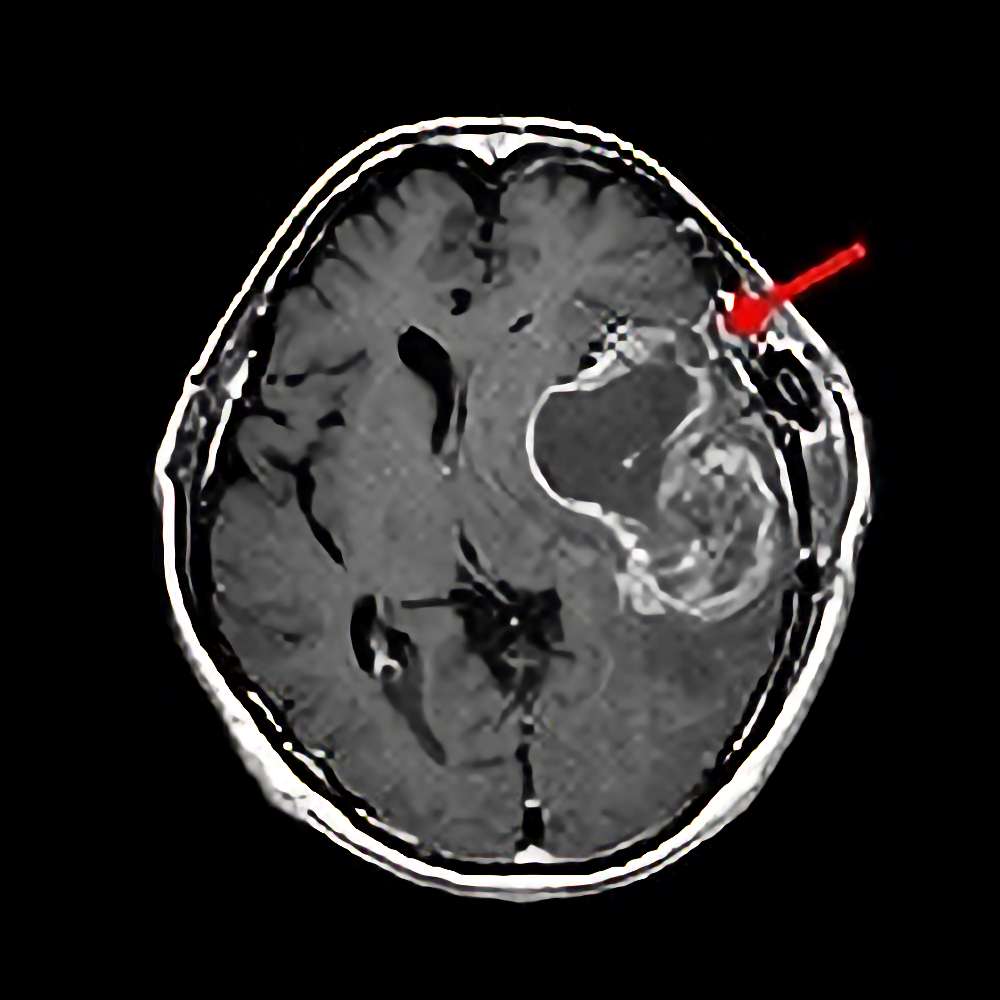

'13年12月

50代

転移性脳腫瘍

No.’13_191 手術前1

No.’13_191 摘出 前

No.’13_191 摘出 後